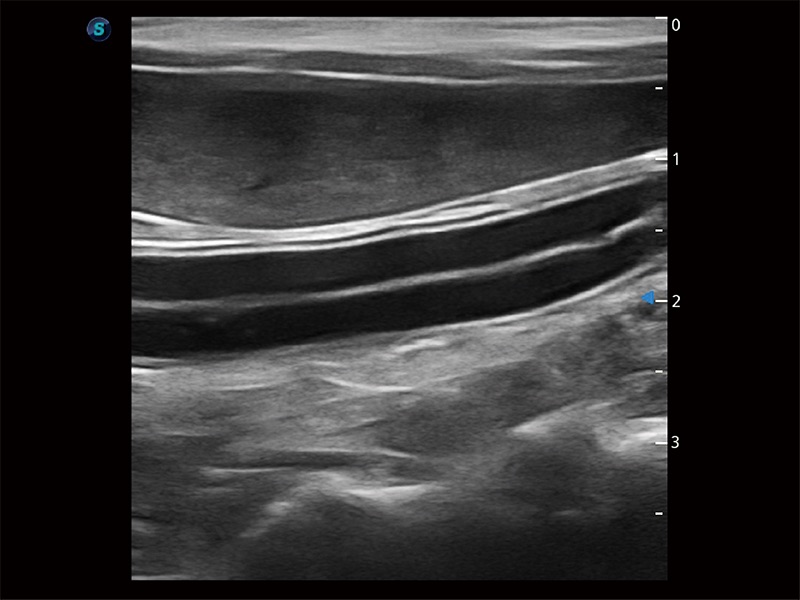

(犬)肠道

了若指掌 腹部/浅表解决方案

高性能和先进的临床应用工具可以为动物医生提供临床信心。ProPet 80 搭载了先进的腹部和浅表应用工具,帮助医生在日常临床实践中发挥前所未有的作用。